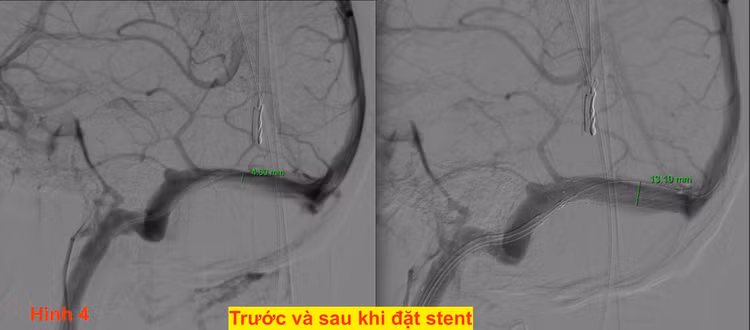

- Bằng việc đo chênh áp trước và sau khi đặt stent mà khẳng định được việc đặt stent là hiệu quả hay không trên hình ảnh.

- Ngay khi mở stent thì BN không còn nghe thấy tiếng thổi là khẳng định việc đặt stent xoang bên là đúng đắn.